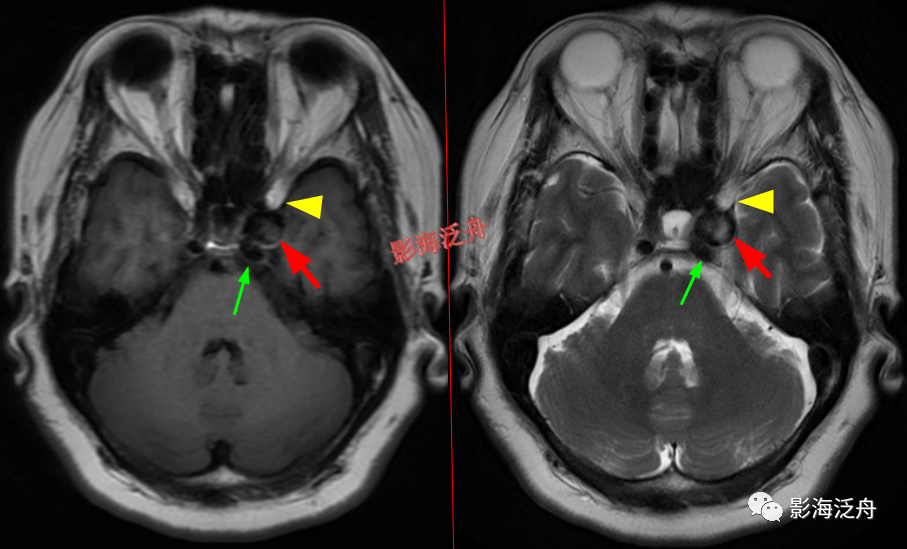

脑膜炎患者,桥前池内可见异常增多的血管影(红箭),正常人的桥前池因为脑脊液流动产生的伪影也可以看到池内絮状低信号(绿箭),但不如右侧患者的明显,这个观察起来比较困难,就如在腹部CT上观察患者是否存在肝脏肿大一样,需要一个经验积累的过程。黄箭指基底动脉,蓝箭指三叉神经。

左侧岩尖部囊性病变(红箭头),患者未术,病理不明。MR对骨质结构显示不佳,因此很多读者会忽略掉颅内骨质病变的观察,很多颅内病变,如三叉神经鞘瘤、鼻咽癌等都会造成颞骨岩部(红色标注区)骨质破坏,因此,平时应对此处多加留意。黄箭头指听神经及内耳结构。

左侧颈内动脉海绵窦段动脉瘤伴血栓形成(红箭),绿箭为海绵窦段起始端,黄箭头所指为颈内动脉分段的重要解剖标志——前床突(颈内动脉分段可参考之前的文章 颈内动脉CTA分段(超实用))。